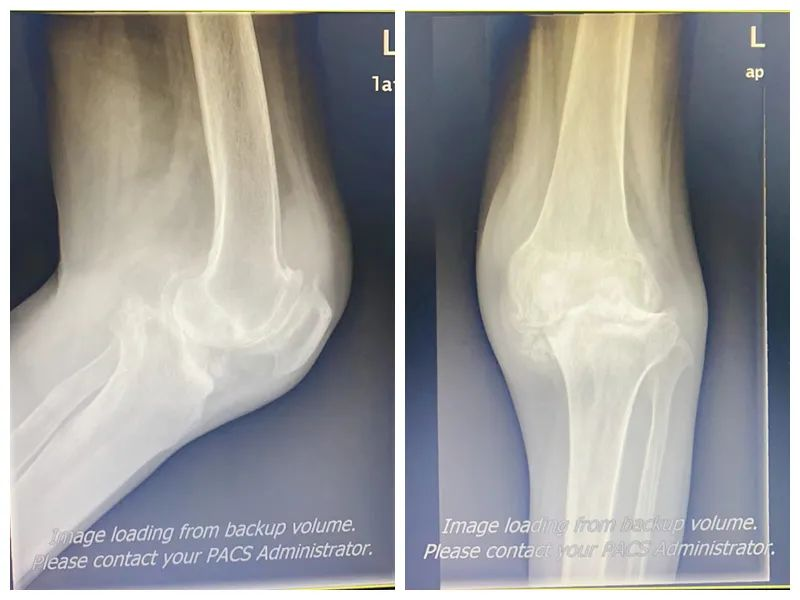

▲患者术前影像

56岁的李阿姨反复双膝疼痛10年,近3年来,无明显诱因下的双膝关节疼痛逐渐加重,上下楼时疼痛明显,活动明显受限。渐渐地李阿姨出现左膝不能行走的情况,需靠轮椅方能出行,严重影响日常生活。患者曾到多家医院就诊,均未得到缓解。为此,李阿姨特意前来我科就诊,经查体后考虑为“双膝关节重度骨性关节炎、左膝关节脱位、类风湿性关节炎”收入院。